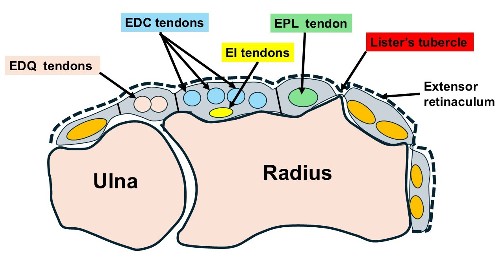

- The EPL = Extensor Pollicus Longus tendon runs along the back of the wrist to the thumb and wraps around Lister’s tubercle, using it as a pulley.

- The muscles are in the forearm. Tendons are like rope joining the muscles to the fingers and thumb. There is a strap of tissue ( extensor retinaculum) on the back of the wrist that holds the tendons down. There are 6 tunnels on the back of the wrist containing the Extensor tendons to the thumb, fingers & wrist.

- This applies particularly when the fracture involves Lister’s tubercle – a prominence on the back of the radius around which the EPL changes direction

- There are 2 tendons that extend the Index finger ( EI & EDC tendons)

- The EI tendon is available for transfer because the EDC tendon to the index finger can still provide normal index finger extension on its own

- The Extensor Indicis (EI) tendon (used to extend the index finger) is redirected to take over the function of the EPL.